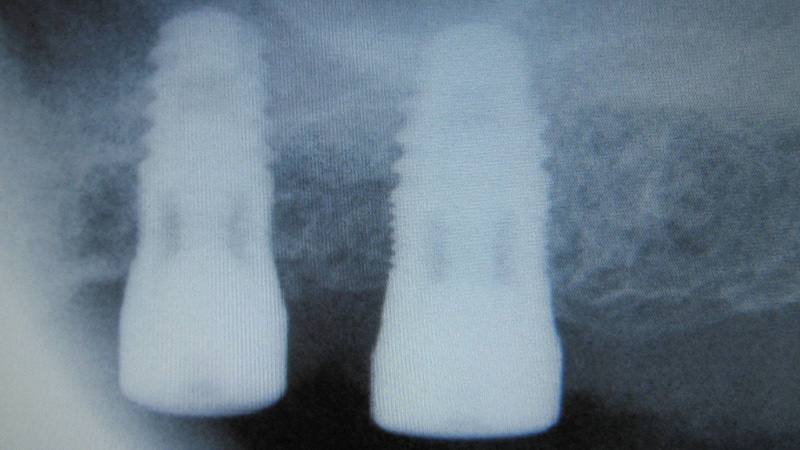

Patient se présentant pour le remplacement de la 26 et 27.

Même dans ce cas où la membrane a été lésée…

10 ans après, notez l’aspect radiologique de la corticale péri-implantaire.